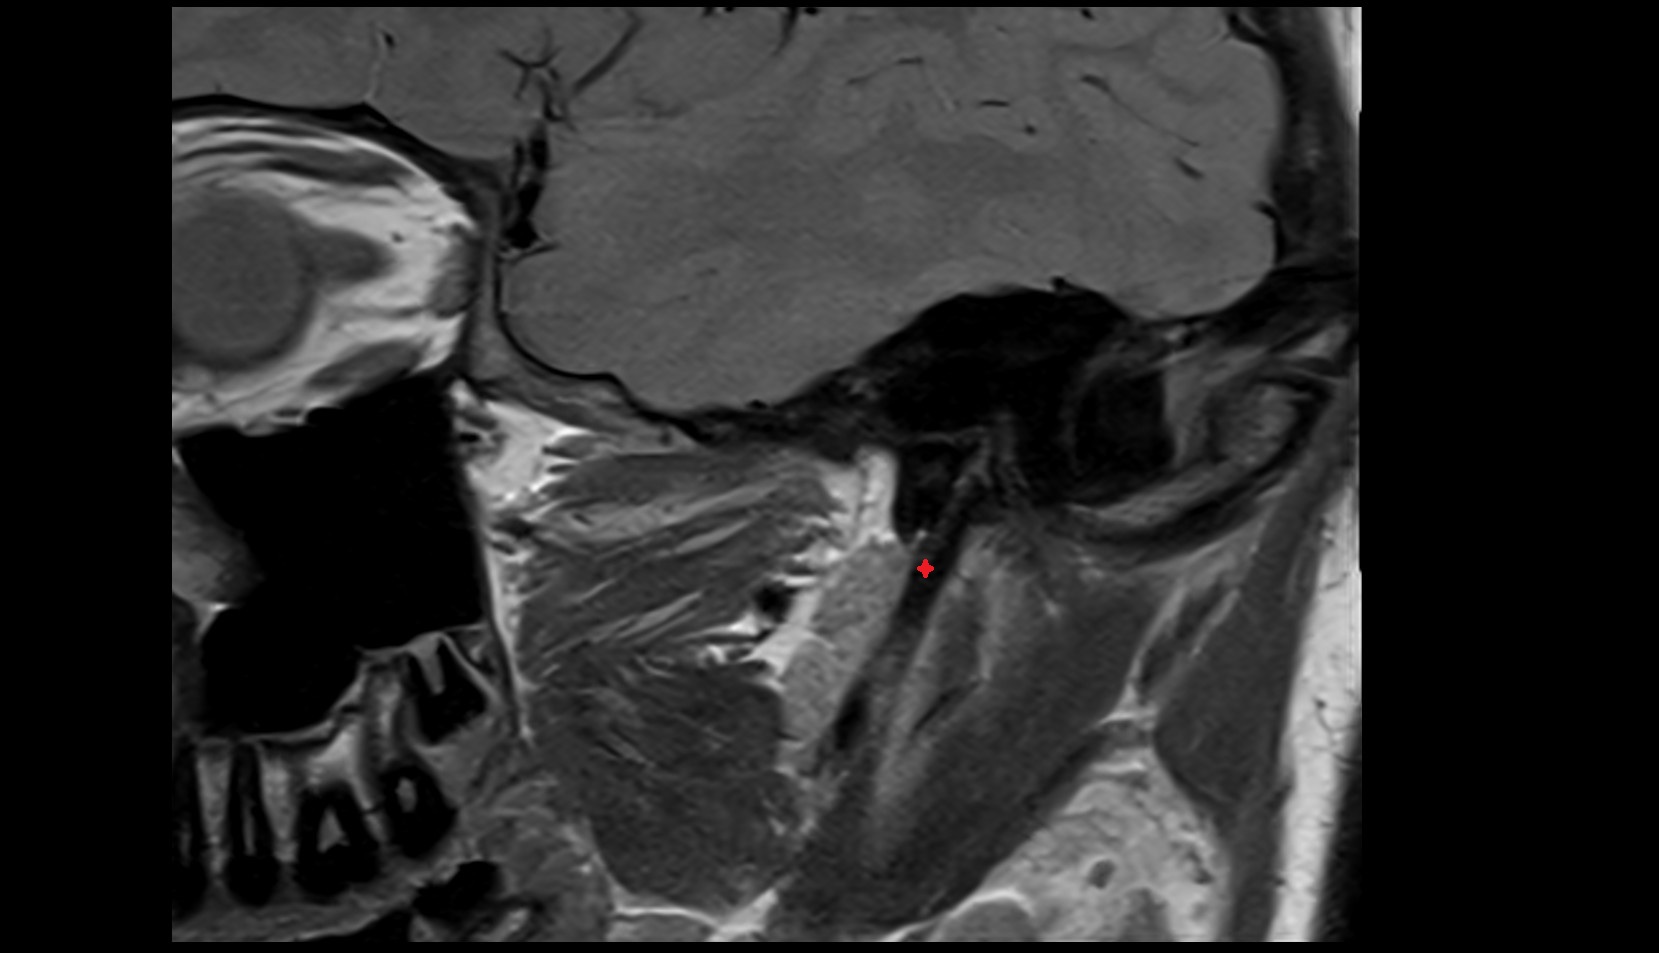

- Articular disc of temporomandibular joint

- Articular eminence

- Articular surface of mandibular fossa

- Intermediate zone of articular disc

- Superior retrodiscal layer

- Temporomandibular joint

- Mandibular condyle

- Mandibular fossa